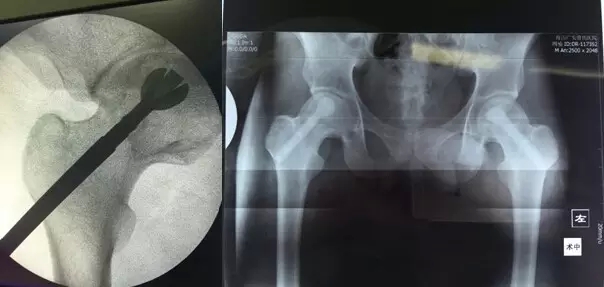

3月29日,舟山廣安醫(yī)院危立軍副院長為一名29歲的雙側(cè)股骨頭早期壞死患者成功實施了股骨頭壞死減壓、病灶清除、可注射人工骨植入術。這是當前國際上在治療此類疾病的最先進的微創(chuàng)手術技術。該項技術可以有效阻止股骨進一步頭壞死而導致關節(jié)軟骨面塌陷,通過再造創(chuàng)面誘導骨再生、成骨而達到治愈目的。

治療股骨頭壞死的關鍵是終止病變進展,在股骨頭壞死的早期階段,保留患者自身髖關節(jié)具有很高的臨床和社會價值。使之有可能往良性的軌道上發(fā)展。廣安醫(yī)院開展的“股骨頭壞死減壓、病灶清除、可注射人工骨植入術”,在保護已發(fā)生的壞死骨基礎上,同時通過生物學反應促進骨再生和病變組織修復,有效恢復承重能力,防止股骨頭變形塌陷。該技術手術切口長約1-2厘米,創(chuàng)傷小,費用低,恢復快,術后第二天即可出院,門診治療。